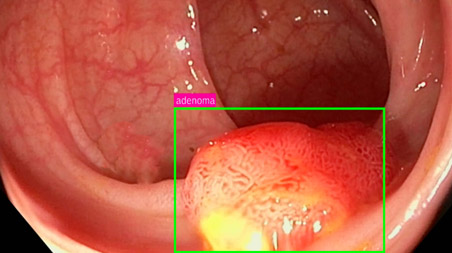

AI applied to the diagnosis of digestive pathologies

The Digestive System team at Olympia Centro Médico Pozuelo will use an artificial intelligence (AI) module in its endoscopy towers to improve the quality and safety of colonoscopy examinations. The AI, called IA Genius, automatically identifies and flags abnormalities consistent with polyps.